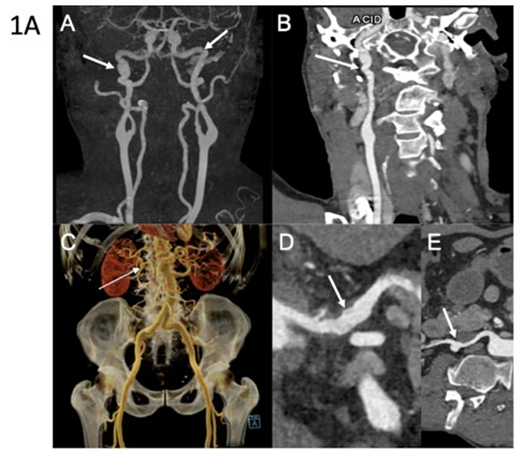

First Case: A 57-year-old man was referred following rupture of a digestive artery aneurysm. He had previously been classified as having FMD based on a history of arterial hypertension and the presence of FMD-like lesions of the right renal artery associated with a cortical defect of the right kidney (Table 1). Updated imaging revealed multiple additional arterial abnormalities, including an aneurysm of the celiac trunk, ectasia of the hepatic and splenic arteries, ectasia of both iliac arteries, and dissection of the right external iliac artery. Both internal carotid arteries displayed a dysplastic appearance, with an associated aneurysm on the right side (Figure 1A). In addition to a history of spontaneous bruising, clinical examination revealed thin, translucent skin and a facial appearance suggestive of vEDS. Genetic testing, performed three years after the initial vascular work-up, identified a heterozygous nonsense variant in COL3A1 (p.Arg562Ter). Cascade genetic testing subsequently identified the same variant in one of his sisters (Figure 2A).

Figure 1A: Arterial imaging of patient 1 on computed tomography angiography (CTA). CTA in a 60-year-old man showing multiple vascular abnormalities. Coronal 3D maximum intensity projection (MIP) reconstruction (A) demonstrates a string-ofbeads appearance of the carotid arteries (arrow). Curved planar reformation (B) shows FMD-like lesions of the right carotid artery (arrow). Coronal volume-rendered image (C) reveals an aneurysm of the right renal artery (arrow). Curved planar reformations of the celiac trunk (D) and the right renal artery (E) show arterial irregularities (arrow) and aneurysmal dilation (arrow). Molecular diagnosis of vascular Ehlers-Danlos syndrome was established after imaging.